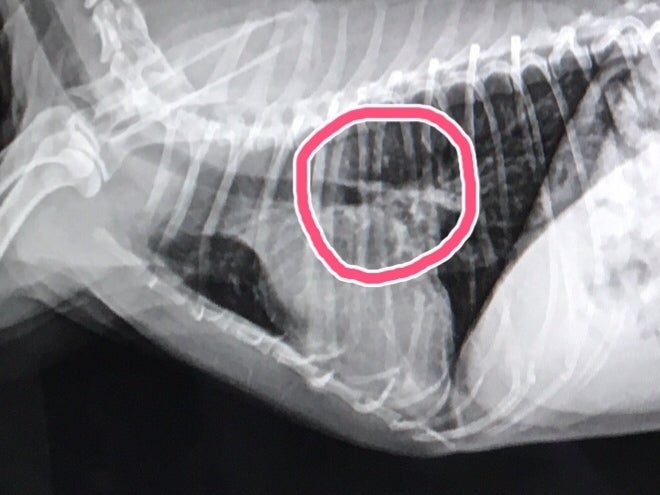

こちらが手術前の心臓です。

心臓の上に気管が通っているのですが、大きくなりすぎた心臓が、気管を押し上げて、気管がつぶれてしまっています。

それが原因で頻繁に咳をしていました。